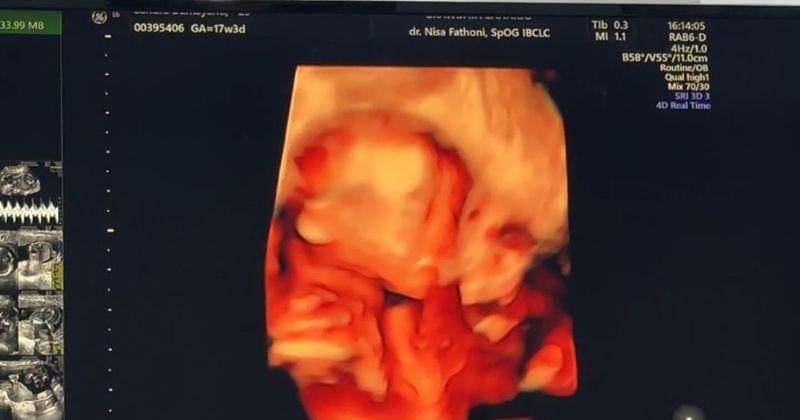

2. Wajah janin dalam kandungan saat trimester kedua nih

Sandra mengumumkan hamil anak pertama di usia kandungan 23 minggu atau di trimester kedua. Baby bump-nya belum besar tetapi cukup terlihat.

Dalam unggahan itu Sandra membagikan foto USG janin dalam kandungannya yang tumbuh dengan baik.

"Masya Allah Tabarakallah.. hihi masih nggak nyangka dikasih rezeki yang luar biasa ini, ada yang hidup di dalam perut besarku hihi semoga kamu bisa bergerak leluasa, sehat selalu ya cinta kicil… #23weekspregnant," tulisnya di caption foto.